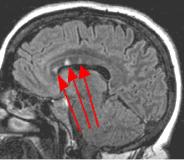

Fig. 2

By turning CSF dark, bright periventricular lesions such as MS plaques become much more conspicuous. Fig. 1 shows a typical T2-weighted axial image of the brain in which CSF in the ventricles appears bright. A lesion on the right is present (red arrow) that is also bright similar to CSF. Fig. 2 is a corresponding FLAIR image showing an obvious bright MS plaque (white arrow) against a background of dark CSF and gray parenchyma with additional more subtle lesions.